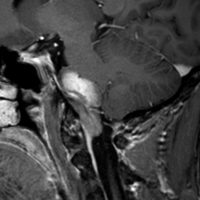

典型的な神経腸嚢胞 neurenteric cyst

左のT2強調画像で等信号,中のT2*で高信号,右はCISS画像です。

T1強調画像では,のう胞周囲の高信号の部分は半固体で,中心部の高信号はドロドロの粘液でした。基本的にガドリニウム増強はされません。まれに薄い膜状に一部が増強されることがあります。

境界明瞭は袋状の腫瘍です。椎骨動脈や脳底動脈を包み込むようにふくらんでいます。

左外側後頭下開頭という小さな開頭手術だけで全摘出しました。術後は幸い何の症状も出ていません。この例は脳幹部に食い込まないもので,運良く全摘できたのですが,そうはいかないものもあります。